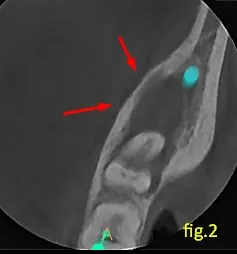

En los cortes axial y transaxial (figuras 2 y 3) se observa que provoca una licuefacción en la medular, abombamiento en la tabla lingual con posterior adelgazamiento, y en algunas zonas se puede observar dificultad para su localización, puede estar relacionada a las caries que presenta en la misma.

Estos signos imagenológicos son compatibles con una osteomielitis crónica.